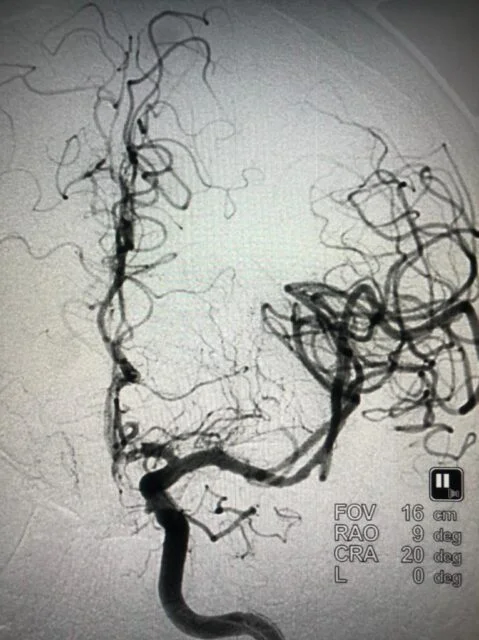

Successful Mechanical Thrombectomy in a relatively young stroke patient at ACCORD SUPERSPECIALITY HOSPITAL - A new hope for a large vessel stroke.